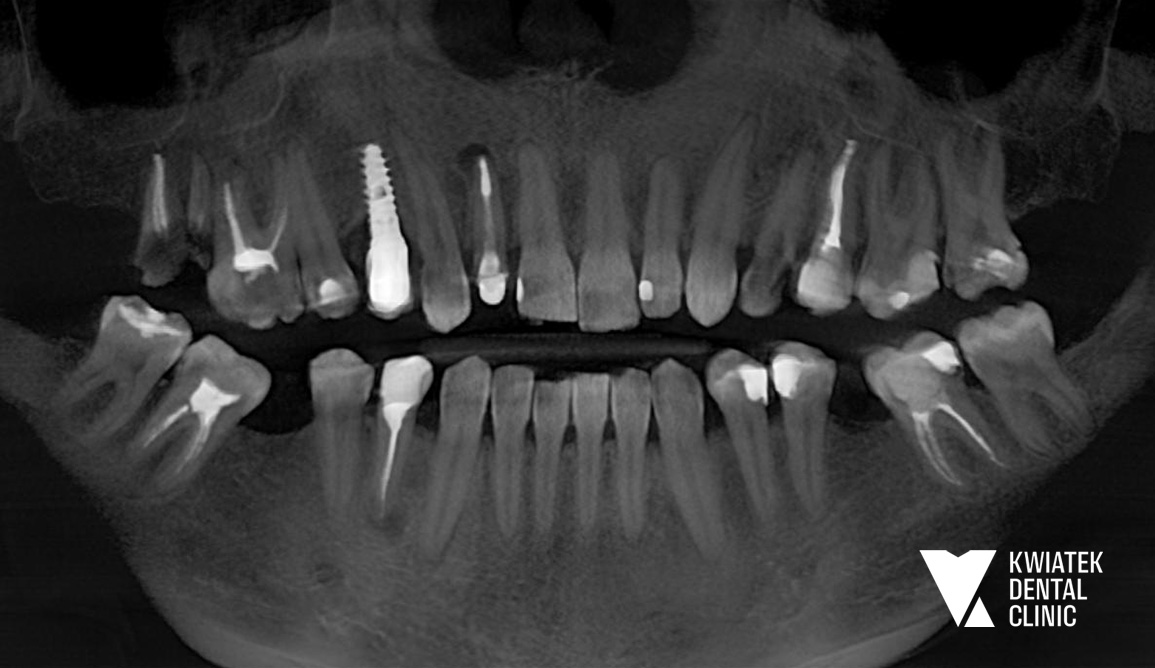

Diagnostyka była prowadzona etapowo z wykorzystaniem tomografii CBCT, skanów wewnątrzustnych oraz dokumentacji radiologicznej i fotograficznej, co pozwoliło na precyzyjne planowanie leczenia w perspektywie długoterminowej.

Rozpoczęto od zabiegów chirurgicznych i usunięcia zębów niekwalifikujących się do leczenia. Następnie wdrożono zaawansowane procedury implantologiczne, w tym natychmiastowe implantacje oraz zabiegi augmentacji kości z użyciem biomateriałów.

W przypadku zęba 24 konieczne było ponowne podejście implantologiczne po braku integracji, które zakończyło się powodzeniem. W odcinku przednim zastosowano nowoczesne techniki implantacji natychmiastowej, zapewniające zachowanie estetyki już na etapie leczenia.